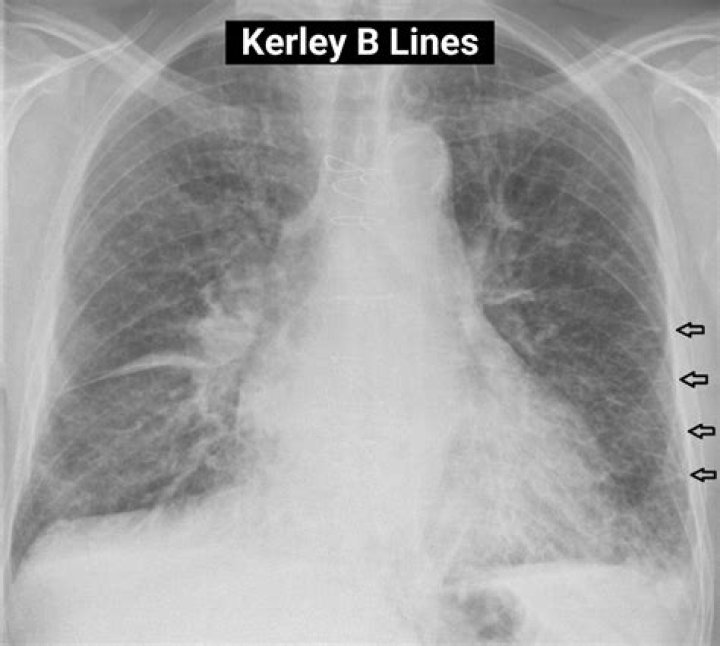

Kerley B lines are small, horizontal, peripheral straight lines demonstrated at the lung bases that represent thickened interlobular septa on CXR. They represent edema of the interlobular septa and though not specific, they frequently imply left ventricular failure.

Kerley B lines These are thin lines 1-2 cm in length in the periphery of the lung(s). They are perpendicular to the pleural surface and extend out to it. They represent thickened subpleural interlobular septa and are usually seen at the lung bases.

Where are Kerley B lines found?

Linear Patterns Kerley’s B lines, which reflect thickening of the subpleural interstitial compartment, typically are about 1 cm in length and 1 mm in thickness and usually found in the periphery of the lower lobes, abutting the pleura.